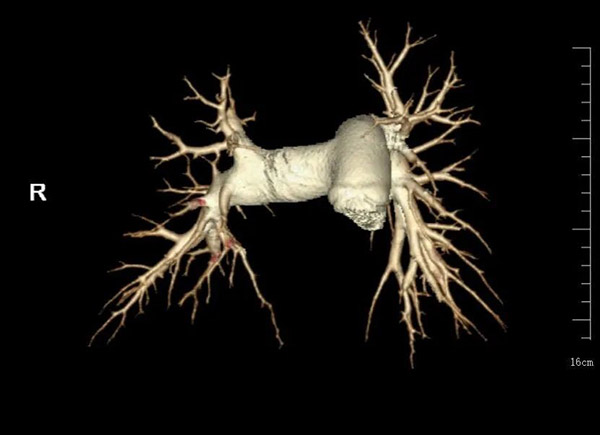

近日,沈阳市第十人民医院(沈阳市胸科医院)呼吸四病区迎来了一位辗转就医1年多的患者。62岁的金女士,平时身体很好,肺炎后总是觉得胸闷气短。她先后去了很多家医院做了肺CT基本正常、血压不高、心电图也没有明显问题。她的邻居和朋友告诉她需要多休息。但是1年多过去了,金女士总是觉得喘气喘不到底,活动后胸闷气短,到底是什么问题呢?呼吸系统及肺血管疾病专家于秀丽主任接诊后,给金女士做了心脏彩超发现她的肺动脉高压高达70mmHg,而正常人心脏彩超肺动脉压力一般不超过37mmHg。于是立刻给她安排肺动脉增强CT及右心导管检查。经肺血管造影及肺动脉测压,发现金女士的肺动脉的压力远远超过正常人,并且在她的肺动脉血管内有较多血栓附着。这些病灶导致她呼吸困难明显,活动耐力下降。最后经过医务人员的及时诊治,金女士的气短胸闷明显好转。

肺动脉高压是一种常见的血液动力学异常状态,涉及多学科、多系统,诊疗难度大,死亡率高,基层认识不足的疾病。目前肺动脉高压临床分为五大类。包括动脉性肺动脉高压、左心疾病所致肺动脉高压、肺病和(或)低氧所致肺动脉高压、肺动脉阻塞所致肺动脉高压、机制未明和(或)多因素所致肺动脉高压。肺血管疾病诊治中需常规完善右心导管术并完善相关检查用于筛查并明确危险因素。而且怀疑肺动脉高压应尽早转诊至诊疗中心。